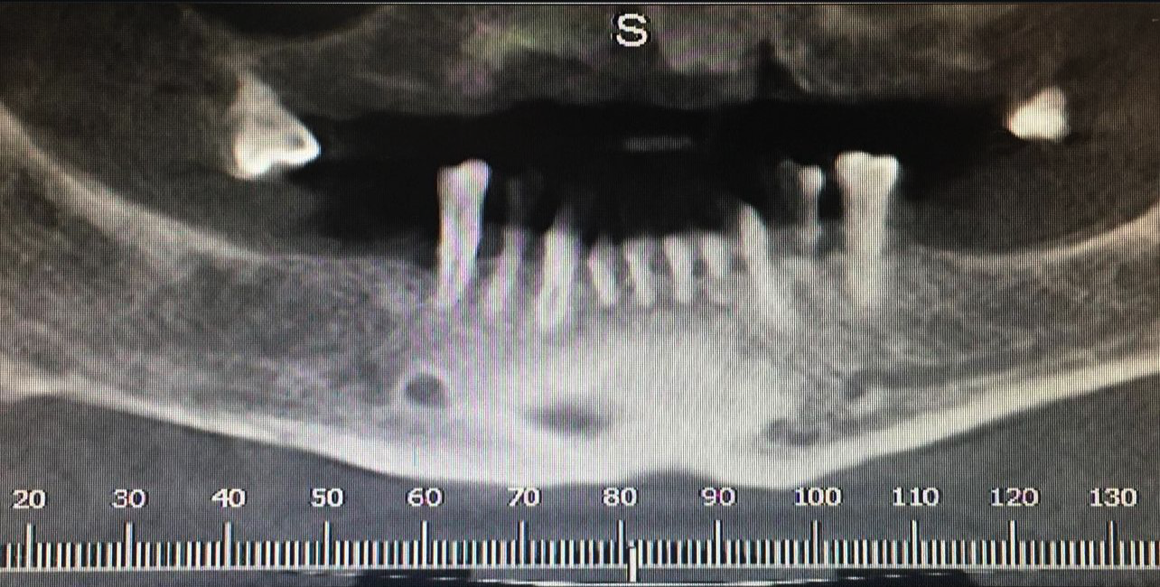

Görselde gördüğümüz o agresif çift sarmal yapı, implantın kemiğe travma yaratmadan, kontrollü ve hızlı bir şekilde yerleşmesini sağlar. Her türlü kemik yoğunluğunda (Tip 1'den Tip 4'e kadar) mükemmel primer stabilite.

MPI All-In System®, modern dental implantolojinin tüm gereksinimlerini tek bir gövdede toplar. İster dar kretler ister sınırlı kemik yüksekliği olsun; All-In teknolojisi, hekime en zorlu anatomik koşullarda bile tam kontrol imkanı tanır.

Sinüs lifting veya kemik ogmentasyonu gibi ileri cerrahi müdahalelere gerek kalmadan, sınırlı dikey kemik mesafesinde güvenli ve estetik sonuçlar sağlar. Daha az cerrahi müdahale, daha hızlı iyileşme süreci ve yüksek hasta memnuniyeti.

Gövde boyunca uzanan çift girişli yiv tasarımı, yerleştirme sırasında kemiği travmatize etmeden aktif bir tutunma sağlar.Özellikle yumuşak kemik tiplerinde bile üst düzey primer stabilite sunarak, "Hemen Yükleme" (Immediate Loading) protokolleri için güvenli bir zemin hazırlar..

Agresif çift girişli yiv geometrisi, implantın kemik içine travma yaratmadan, kontrollü bir şekilde ilerlemesini sağlar. En yumuşak kemik tiplerinde bile üstün primer stabilite ve hemen yükleme (immediate loading) imkanı.